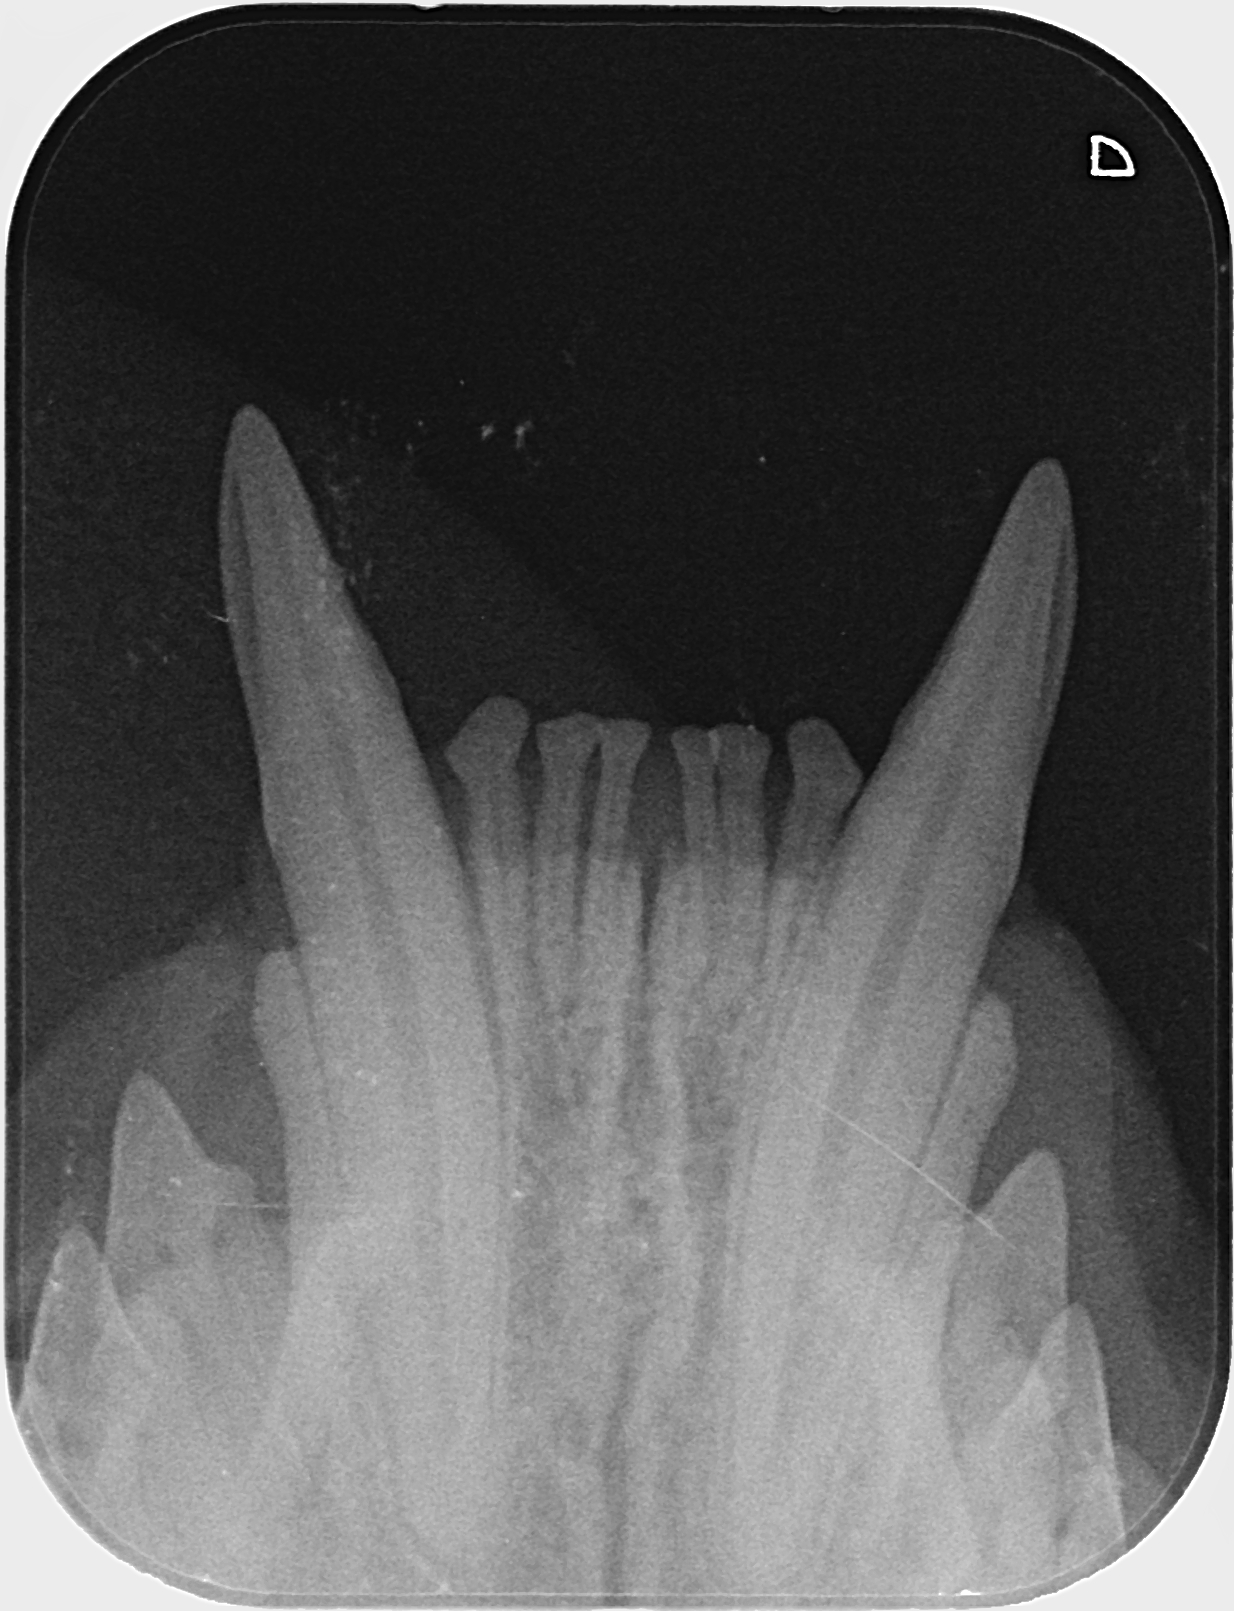

Kissan hampaat voivat näyttää päällisin puolin ihan hyvältä, mutta hampaiden juurissa voi olla piileviä ongelmia. Ainoa tapa selvittää, ovatko hampaat oikeasti kunnossa, on ottaa hammasröntgen.

IC Moggi Sikuri Sakari(Kilju) piipahti jo jonkin aikaaa sitten Amyvetissä hammahuollossa ja samassa kalusto pääsi kuviin. Tulos oli juuriaan myöten terveet hampaat. Hammaskiven poistoa pienesti ja ohjeeksi harjailla hampaita ahkerasti.

Ohessa muutama kuva malliksi.